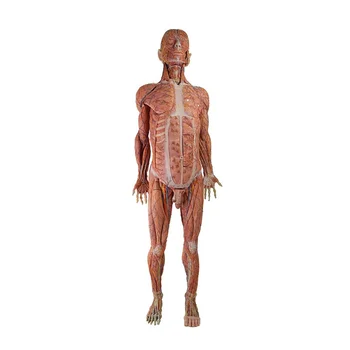

Zhengzhou Meiwo Science & Technology Co., Ltd established in 2009, is a comprehensive technology enterprise for medical education integrating R&D, production and sales. Meiwo Science has independent specimen production workshops and model production workshops covering an area of 10,000 square meters. Meiwo main products involve plastinated animal specimens, soft silicone anatomy models, high simulation soft anatomy models, human & animal anatomy softwares, 3D digital human specimen, biological microscope slides, animal skeletons, etc.